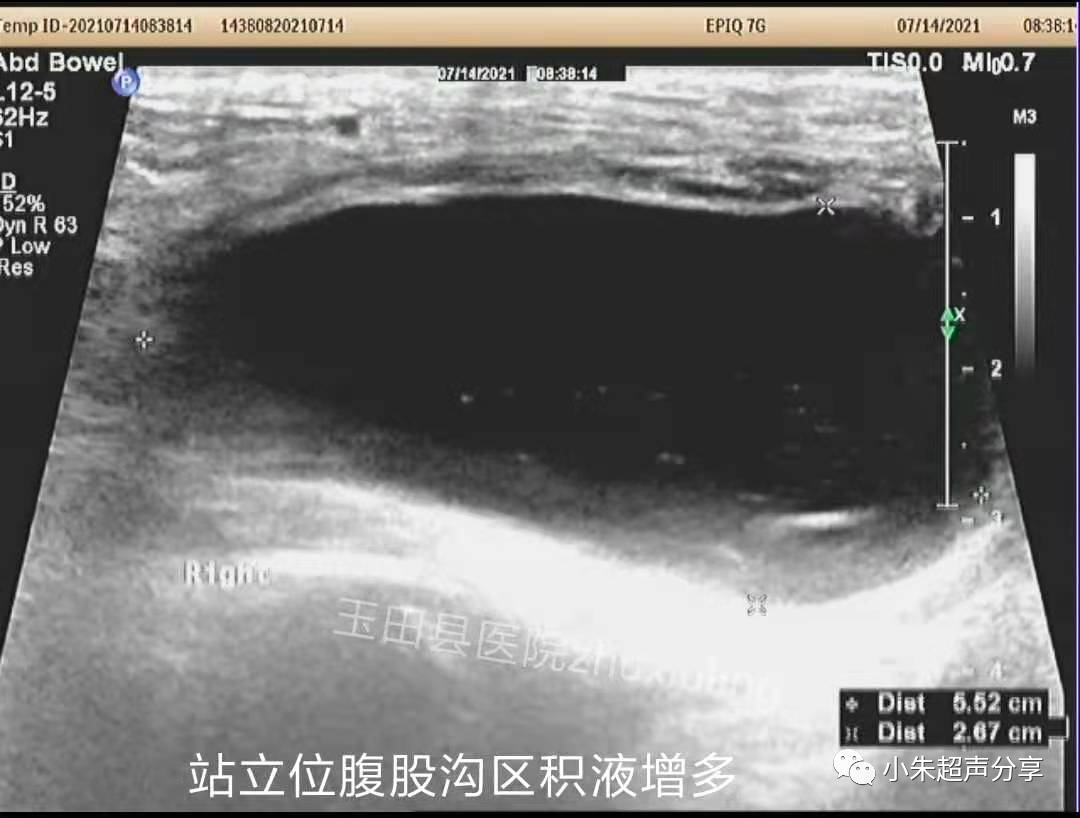

与临床医生沟通后,临床医生行超声引导下腹股沟区抽液。站立位,抽出淡红色液体约50ml。

抽液后,右下腹液体减少、消失。补片紧贴前腹壁。

血清肿常表现为边界不清、形态不规则、透声差的无回声区,持续时间长者积液内可见多发分隔,无血流信号。在其内部或周边常可见到补片结构,病程长者,补片可卷曲变形呈波浪状(如Case2)。发现时应及时与手术医生沟通,必要时需多次穿刺抽吸,并需定期复查。Case1患者经抽液2次后好转出院(第1次抽出50ml淡红色液体,隔日抽出45ml淡黄色液体)。Case2患者经门诊保守治疗后痊愈。

该2例患者积液发生的部位亦有所不同,Case1患者积液位于右下腹腹腔内并与腹股沟区相通(考虑积液位置为原疝囊内),可能残留狭小缝隙,但未见腹腔内容物疝出;Case2患者积液局限于腹股沟区腹壁软组织内,未见与腹腔相通。